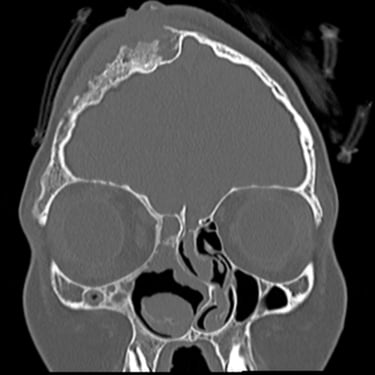

Osteomielitis Frontal | Diagnóstico por Tomografía

La osteomielitis frontal es una infección del hueso craneal que generalmente se origina como complicación de una sinusitis frontal no tratada o mal resuelta. Clínicamente puede manifestarse con dolor localizado, fiebre, edema frontal y signos inflamatorios en la región afectada. El método diagnóstico de elección es la tomografía computarizada (TC), que permite identificar destrucción ósea, engrosamiento cortical e incluso colecciones asociadas. Este estudio es esencial para diferenciarla de otras lesiones y planificar un tratamiento adecuado, que puede incluir antibióticos de amplio espectro y cirugía para drenar y desbridar el tejido infectado, evitando complicaciones intracraneales graves.